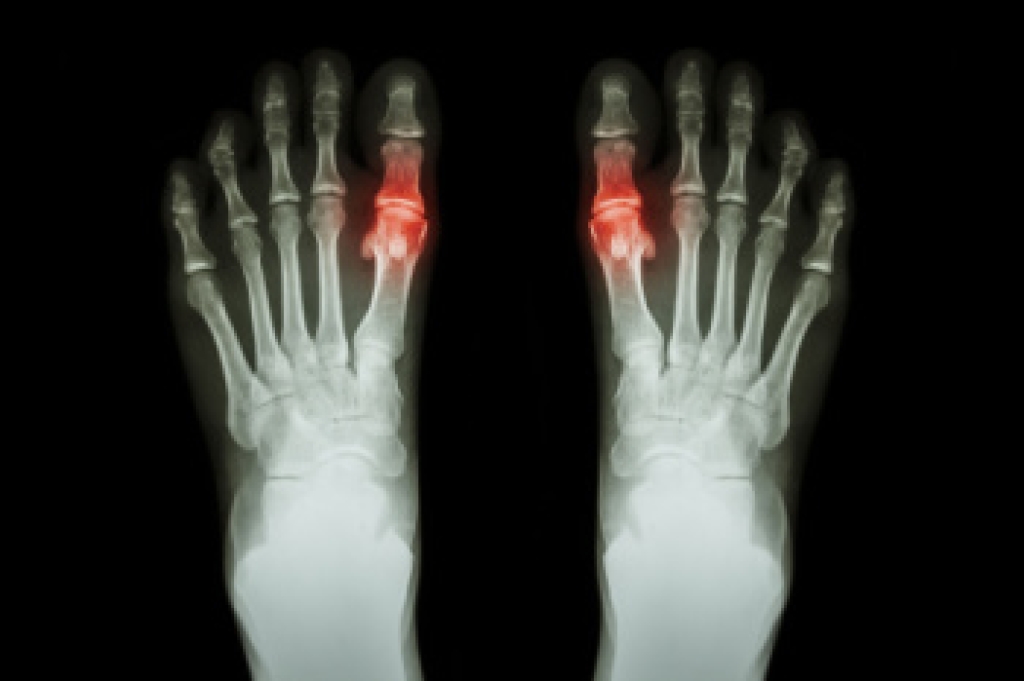

Older individuals usually suffer from heel spurs and pain sometimes intensifies with age. One of the main condition's spurs are related to is plantar fasciitis.

The pain associated with spurs is often because of weight placed on the feet. When someone is walking, their entire weight is concentrated on the feet. Bone spurs then have the tendency to affect other bones and tissues around the foot. As the pain continues, the feet will become tender and sensitive over time.